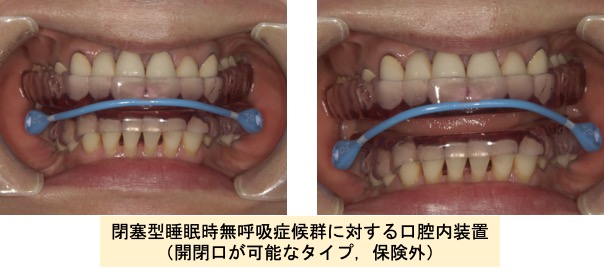

閉塞型睡眠時無呼吸症候群(OSAS)の治療

睡眠時無呼吸症は、睡眠中の呼吸減少や停止により、体内の酸素濃度が減ったり、脳が覚醒したりと睡眠が障害される病気です。多くは、上気道が舌や軟口蓋でふさがれることによって発症する閉塞型睡眠時無呼吸症で、大きないびきは、その兆候といわれています。

歯科では主に軽症から中等症を対象とし、専用のマウスピースを用いた対症療法が行われています。マウスピースは下顎や舌を前方に固定し、気道を確保する装置で、簡便さなどから広く受け入れられている治療です。

なお保険診療にてマウスピースの治療を行う場合、医科の医療機関での診断と紹介状が必要となります。またマウスピース装着後は、治療の効果をみるために再度紹介元の医科医療機関の受診が必要となります。